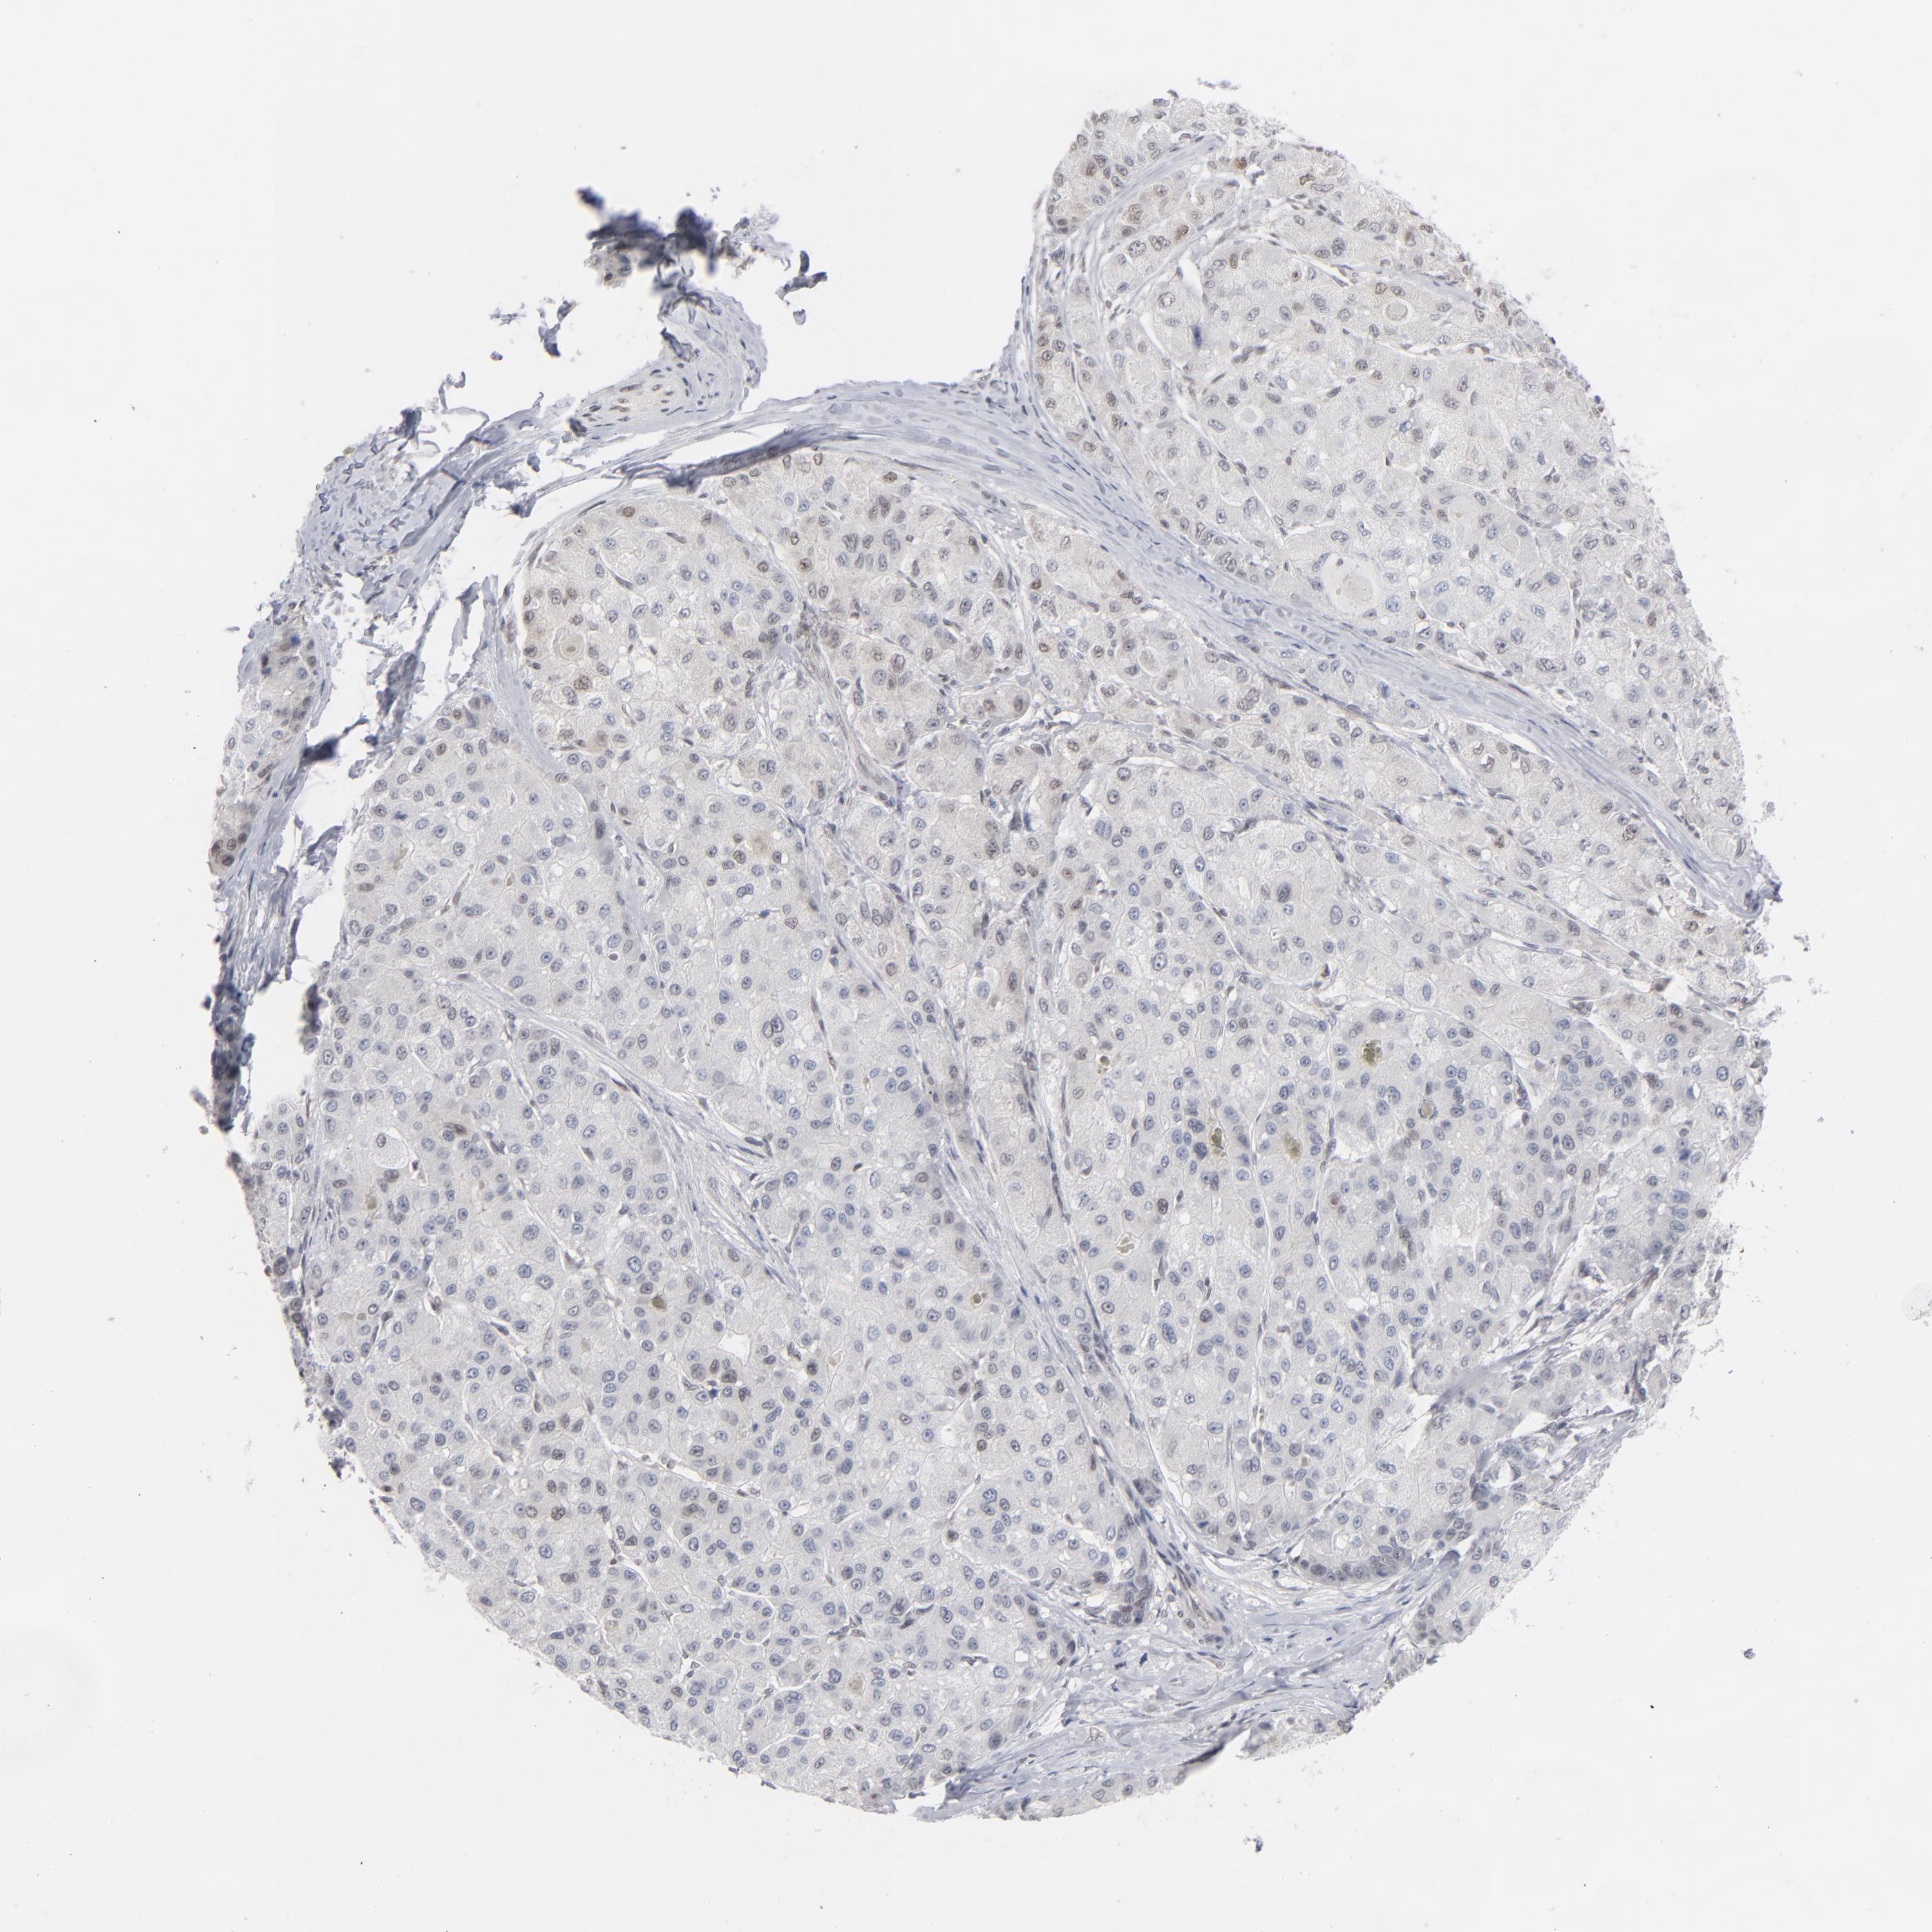

LIVER CANCER - Protein expressioni

A mouse-over function shows sample information and annotation data. Click on an image to view it in a full screen mode. Samples can be filtered based on level of antibody staining by selecting one or several of the following categories: high, medium, low and not detected. The assay and annotation is described here.

Note that samples used for immunohistochemistry by the Human Protein Atlas do not correspond to samples in the TCGA dataset.

Antibody stainingi

Antibody staining in the annotated cell types in the current human tissue is reported as not detected, low, medium, or high, based on conventional immunohistochemistry profiling in selected tissues. This score is based on the combination of the staining intensity and fraction of stained cells.

Each image is clickable and will lead to virtual microscopy that enables deeper exploration of all samples and also displays staining intensity scores, fraction scores and subcellular localization as well as patient and tissue information for each sample.

Antibody HPA001862

Staining

High

Medium

Low

Not detected

Intensity

Strong

Moderate

Weak

Negative

Quantity

>75%

75%-25%

<25%

None

Location

Nuclear

Cytoplasmic/membranous

Cytoplasmic/membranous,nuclear

Cholangiocarcinoma

Carcinoma, Hepatocellular, NOS